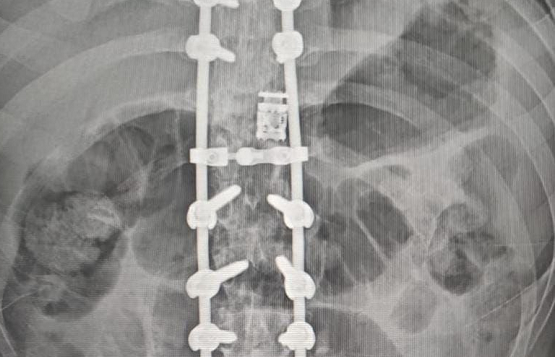

Dr. Somashekar D is an experienced spine surgeon in Bangalore. He is currently practising as a Consultant - Spine Surgery at Manipal Hospital Jayanagar, Bangalore. With nearly 10+ years of expertise in spine care, Dr. Somashekar has established himself as a highly skilled spine surgeon, contributing to over 1,500+ spine surgeries independently, ranging from simple decompressions to complex spinal reconstructions. His practice is deeply rooted in precision-based techniques and evidence-guided clinical protocols, ensuring both safety and long-term functional outcomes for his patients. He is a top spine surgeon in Jayanagar.

We offer comprehensive treatment for spine issues that is on par with any leading spine center worldwide. Our services encompass both non-surgical and surgical treatments tailored to address your specific condition. Our expertise covers a wide range of spine surgeries, including minimally invasive spine surgery, cervical spine surgery, scoliosis surgery, and complex spine surgeries.

Covers a wide range of spine surgeries, including complex spine surgeries.